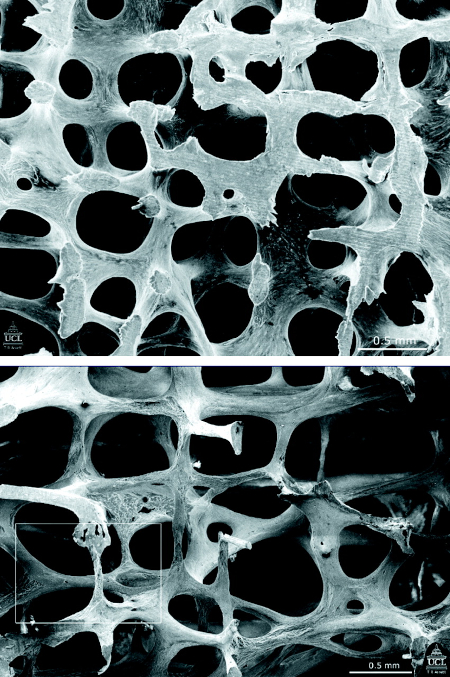

Eletromicrografia de varredura que mostra a estrutura da vértebra L3 em uma mulher de 31 anos (parte superior) e em uma mulher de 70 anos (parte inferior). Observe que muitas das estruturas tipo placa se converteram em bacilos finos

Poole KES, et al. BMJ 2006; 333: 1251; usado com permissão